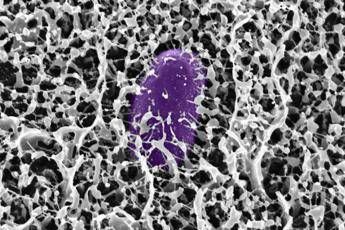

Come ha spiegato la ricercatrice Kelsey Wheeler, co-autrice principale dello studio: “I mimic della mucina brillerebbero in particolare come preventivi, perché è così che il corpo ha evoluto il muco, come parte di questo sistema immunitario innato per prevenire l'infezione”. La strategia si basa sull'idea di rafforzare le barriere mucose nelle aree del tratto gastrointestinale che la Salmonella tende a infettare. La ricerca è stata sostenuta da diversi enti, tra cui l'U.S. Army Research Office, l'U.S. National Science Foundation e il National Institutes of Health. Immagine di cover per gentile concessione dei ricercatori del MIT —[email protected] (Web Info)